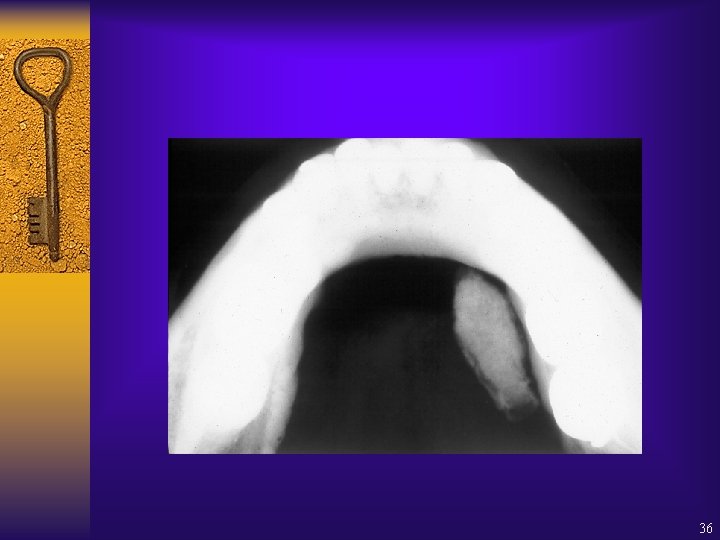

Supernumerary tooth – where is it? 37

38